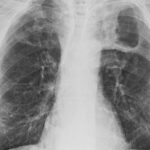

Tuberculosis

In this episode Merle and Lee speak with Eric Story (Western University) about his work on tuberculosis in the Canadian army during World War I. Eric begins by discussing disability studies and tuberculosis before focusing on the Canadian military during the war. As a social historian, Story examines the impacts of tuberculosis on different groups in Canadian society. He then expands on some of the attempts to treat tuberculosis through sanatoria while also calling attention to the fact that Canadian governments took care of soldiers’ present and future, investing substantial resources for this purpose. The conversation also includes a reflection on writing about tuberculosis during Covid, public health and the forgetting(?) of Covid.